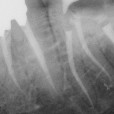

3/3 Postoperative x-ray Glide path with One G, Preflaring with One flare, Shaping with One curve in three waves up to the apex.